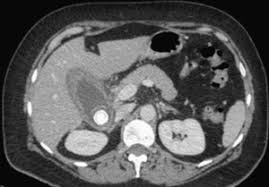

I polipi di colesterolo della colecisti non richiedono, quindi, alcun trattamento, in considerazione del fatto che nel 95% dei casi non modificano mai le loro dimensioni. Non devi contare su esami medici dubbi; Polipi della colecisti, colecisti a porcellana (una colecisti calcificata che può nascondere una neoplasia), colecistite in assenza di calcoli della colecisti. Consulti online su medicina live. Scendendo nello specifico, ecco i cibi da preferire: L'alimentazione dovrà essere del tutto regolare, evitando esclusivamente pasti eccessivi ed abbondati in cibi grassi. > terapie a base di gemmoderivati: Analizziamo quali sono i sintomi che caratterizzano questa patologia, in quali casi è possibile tenere il problema sotto controllo con una dieta e quando invece, è necessario ricorrere all'operazione. I polipi di colesterolo sono riconducibili all'accumulo di colesterolo all'interno di particolari cellule spazzino, i macrofagi, da cui l'accrescimento graduale della parete. In realtà, da tempo è noto che la stragrande maggioranza di polipi della colecisti sono asintomatici e non richiedono alcuna terapia riservando l' intervento di colecistectomia ai polipi di maggiori La colesterolosi che è alla base della formazione dei polipi nella parete della colecisti è caratterizzata dall'accumulo di trigliceridi in particolari cellule (i macrofagi) della parte di parete che si chiama lamina propria. La letteratura scientifica in materia è prodiga di dati, in molti lavori si è tentato di fare chiarezza su una questione essenziale che si può riassumere così: Tre anni or sono, a seguito di leggeri problemi di digestione, ho eseguito esame ecografico del fegato e delle vie biliari.

La maggior parte dei polipi della colecisti si forma a causa dei calcoli. Analizziamo quali sono i sintomi che caratterizzano questa patologia, in quali casi è possibile tenere il problema sotto controllo con una dieta e quando invece, è necessario ricorrere all'operazione. Cura e terapia dei calcoli biliari. Sia l'ecografista che il mio mio medico ha detto che i doloretti non sono riferibili a questi polipi, mi hja consigliato comunque di mettermi a dieta, e in effetti, da quando ho limitato fritti. La colesterolosi che è alla base della formazione dei polipi nella parete della colecisti è caratterizzata dall'accumulo di trigliceridi in particolari cellule (i macrofagi) della parte di parete che si chiama lamina propria. Gentile dottore, volevo chiedere un informazione, ho 4 polipi alla cistifellea il più grande misura 4 cm, voglio evitare l'intervento chirurgico più che altro perchè soffro di diverse fobie e di attacchi di panico, volevo chiederle se ci fosse oltre ad una dieta bilanciata una qualche cura o terapia che potesse aiutarmi a non peggiorare la mia situazione, ci tengo a dire che non avverto sintomi particolari se non qualche piccola fitta in seguito ad abbuffate con cibi grassi o. Ricordo che dopo l'intervento ho dovuto mangiare leggero (niente formaggi, fritti, uova, ecc.) per 15 giorni, poi ho ripreso la mia alimentazione regolarmente, mangio di tutto e sto benissimo; L'adenomiomatosi è una condizione di causa sconosciuta caratterizzata dall'iperplasia dei tessuti della parete colecistica, con conseguente estroflessione della mucosa all'interno del lume. Un polipo al fegato o meglio, nello specifico alla colecisti, può essere pericoloso?e cosa fare? E' questo il quesito giunto alla nostra redazione per la rubrica chiedi all'esperto: Comuni dopo i 40 anni, alla vista si presentano come irregolarità della mucosa, ovvero la parete del colon o del retto. I polipi di colesterolo sono riconducibili all'accumulo di colesterolo all'interno di particolari cellule spazzino, i macrofagi, da cui l'accrescimento graduale della parete. La colecistite è una patologia infiammatoria a carico della cistifellea o colecisti.